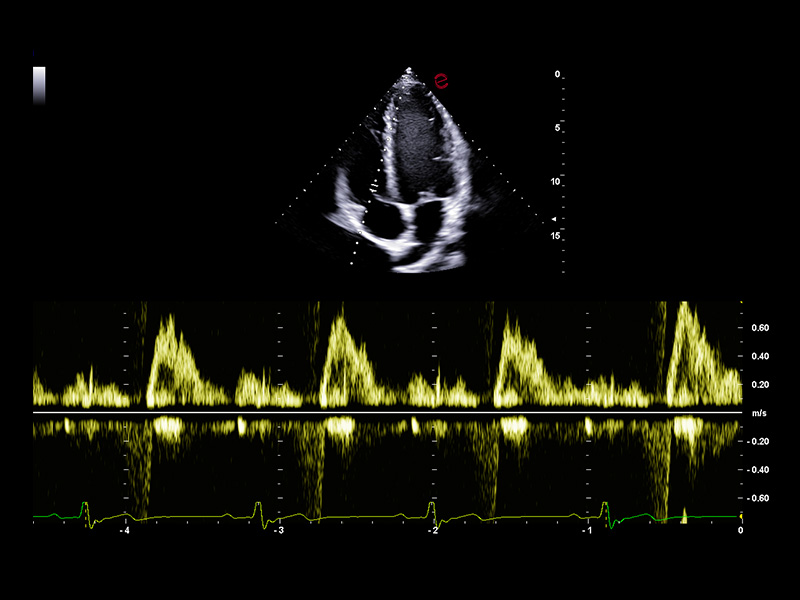

Innovative hemodynamic assessment with HyperDoppler

Esaote’s HyperDoppler technology provides an advanced visualization of intracardiac blood flow dynamics, offering clinicians an intuitive understanding of complex hemodynamics that goes beyond conventional Doppler imaging. By generating real-time vector maps, streamlines, and vortex formations, HyperDoppler enables the detailed assessment of diastolic function, ventricular dyssynchrony, and valvular abnormalities.

This unique flow visualization supports earlier detection of subtle dysfunction, particularly in challenging cases such as heart failure, prosthetic valve evaluation, and structural heart disease. HyperDoppler’s zero-click, visually rich interface enables faster, more comprehensive exams, allowing cardiologists to make more informed clinical decisions.